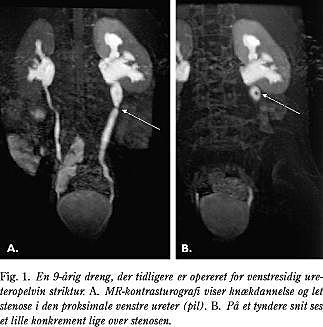

MR-kontrasturografien er at foretrække, når urinvejene er normalt kalibrerede. Den giver præcise oplysninger om selv små fyldningsdefekter og kortlægger meget præcist en stenose og eventuel kontrastpassage gennem denne (Fig. 1). Metoden forudsætter en vis nyrefunktion, men da MR-scanningen er uhyre følsom for selv meget små mængder kontrast, vil man kunne se kontrastudskillelse hos patienter, hvor den konventionelle urografi må give op pga. manglende udskillelse. MR-kontrasten har en meget lille nefrotoksisk effekt og kan uden problemer gives til patienter med nedsat nyrefunktion.